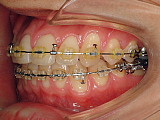

| できたスペースをうまく利用して前歯を並べていきます。 |